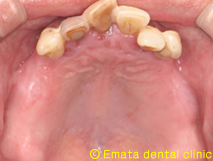

現在世界で最もインプラント治療を手がけているポルトガルのP.マロ先生よりAll-on-4(オールオンフォー)と呼ばれるコンセプトが提唱されました。

All-on-4(オールオンフォー)とは従来のインプラント治療に大きな変革をもたらす、画期的で最新の治療方法です。たった4本から6本でインプラントで12本分の歯を支えることを可能で手術が終わったとたんに入れ歯から開放され、固定式の歯がはいります。

では治療例をみてみましょう。

| All-on-4は4本ではないかとおもいますが、骨の状態や対合歯が自分の歯なのでより確実性をもたせたいため5本で立ち上げ、2本はスリープさせました。

この症例のポイントは、ソケットリフト部位への即時負荷でしょう。アダプテーションテクニックにより40ニュートンの初期固定がえられました(専門的になってしまいましたね)。 麻酔専門医の先生が静脈内鎮静法を行っていますので患者さんは半分寝ているうちに手術が終わってしまいます。 |